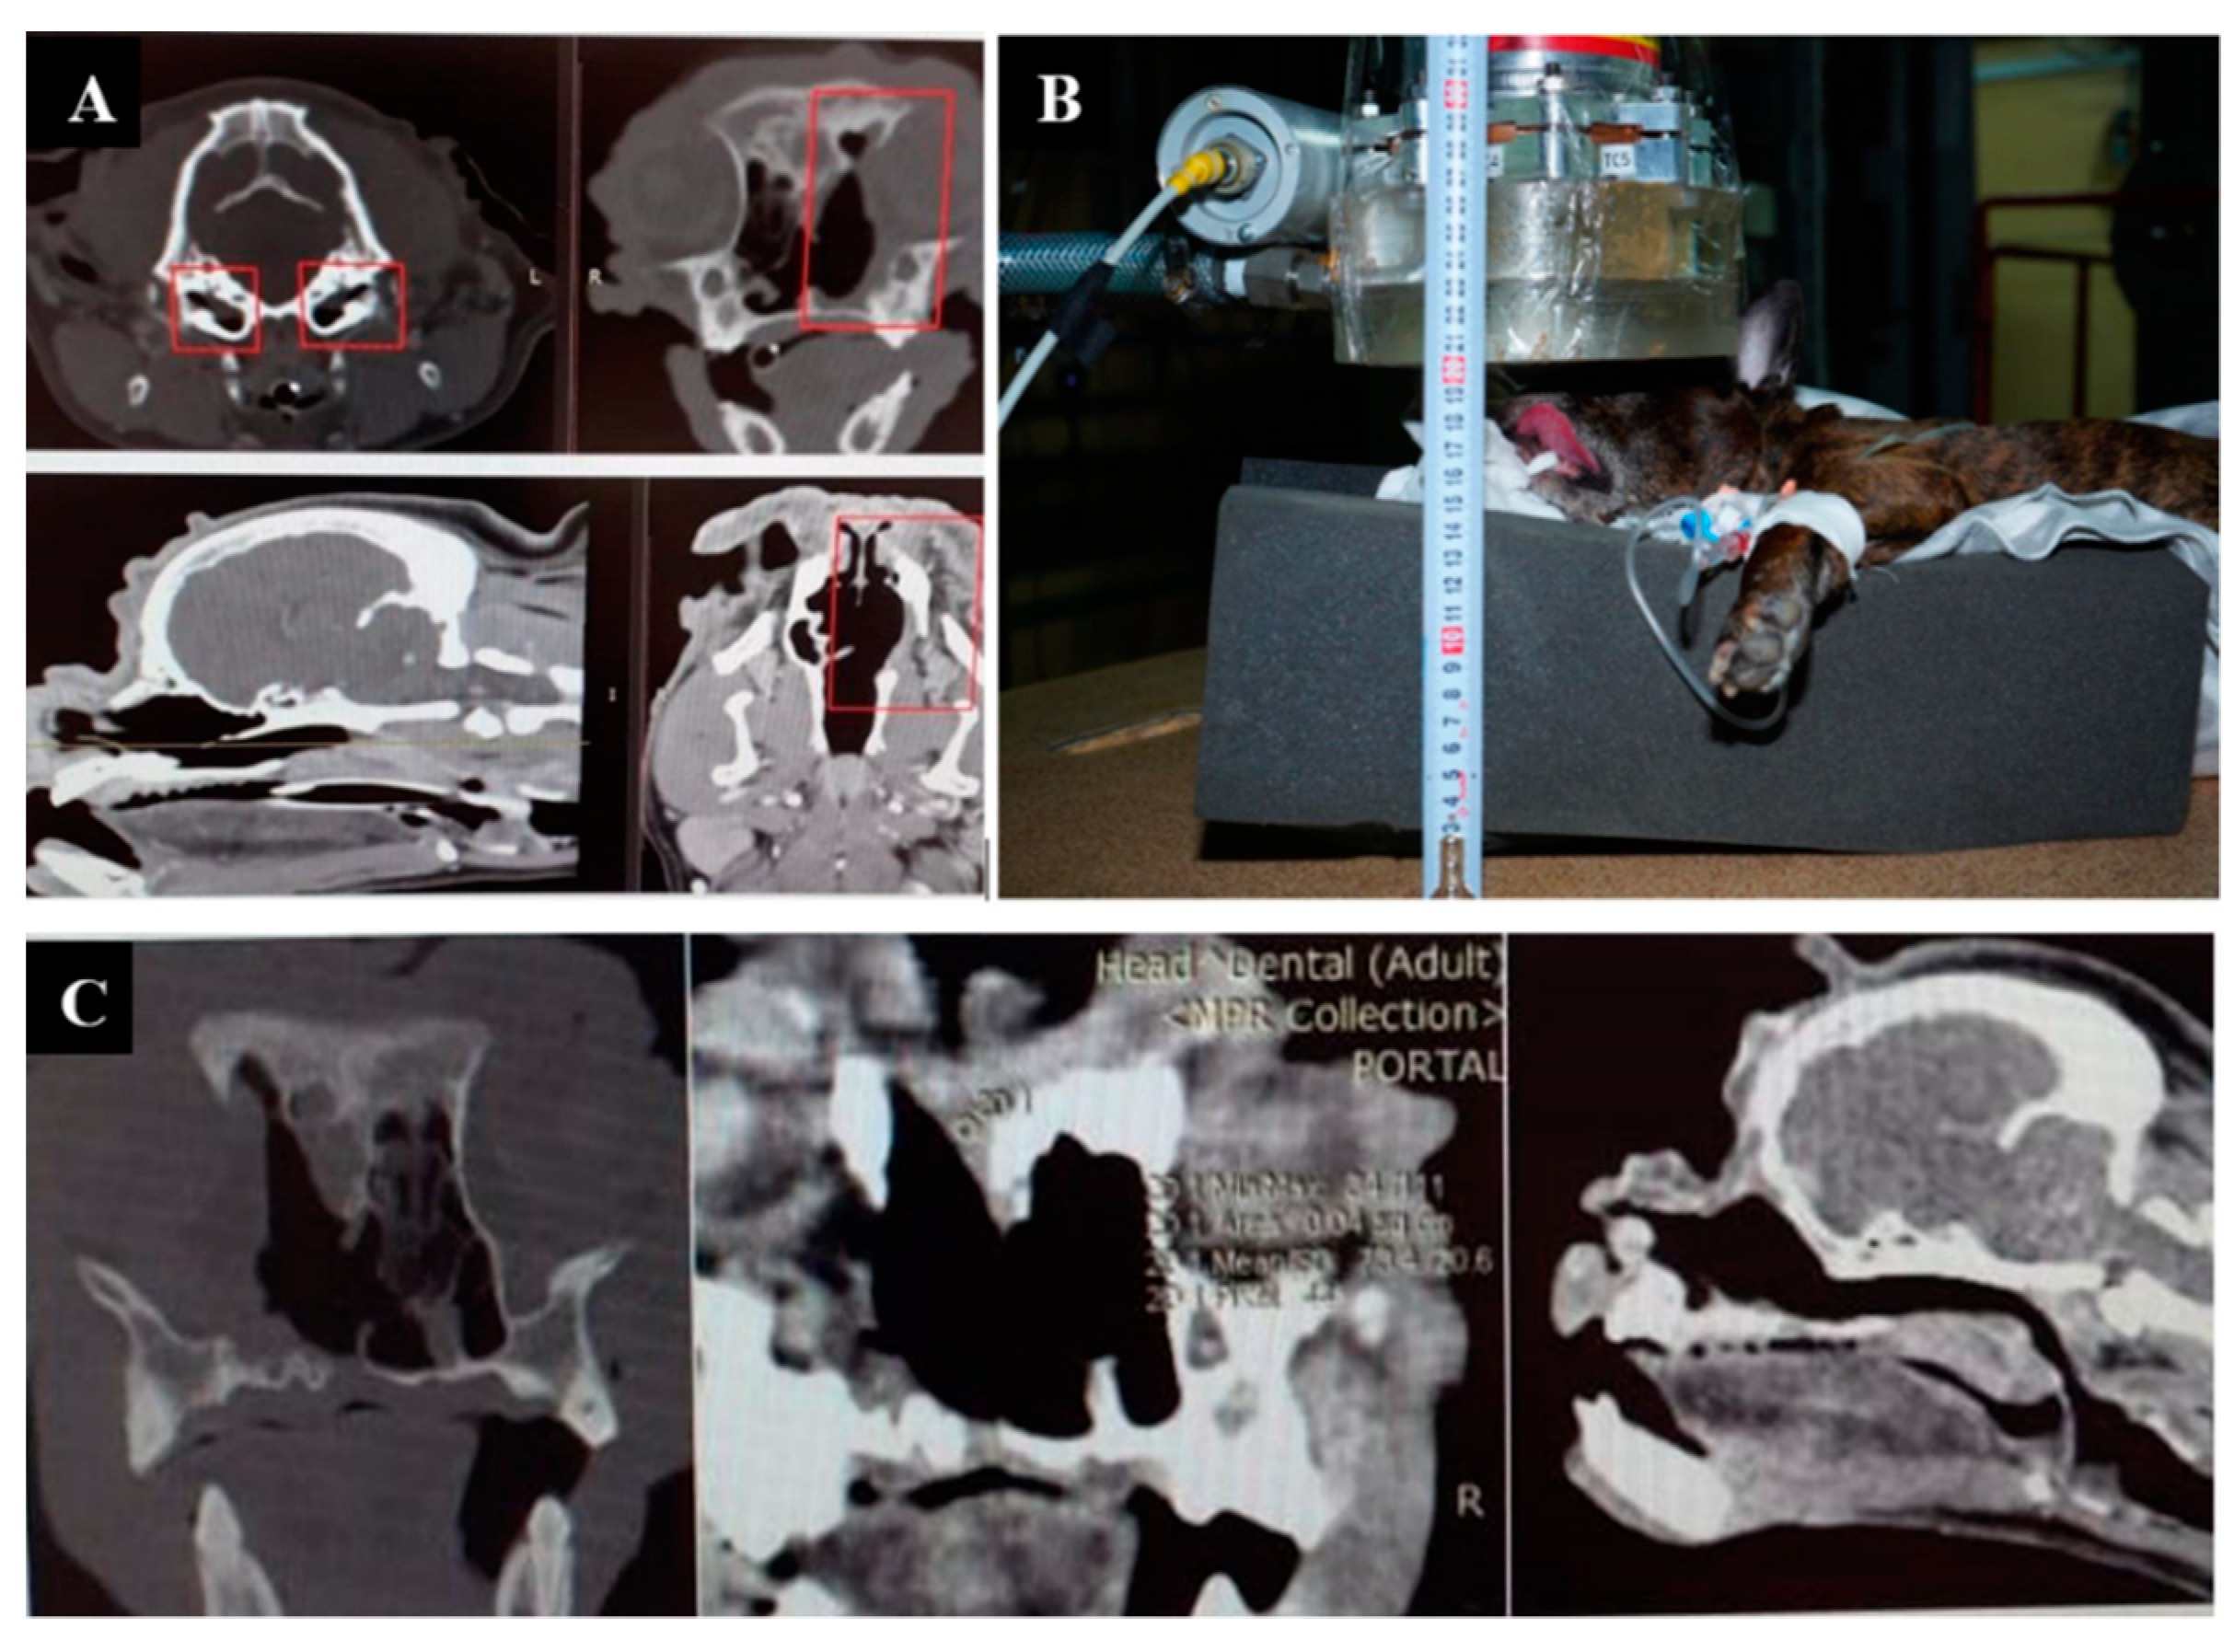

3.1. Case 1

3.2. Case 2

3.3. Case 3

3.4. Case 4